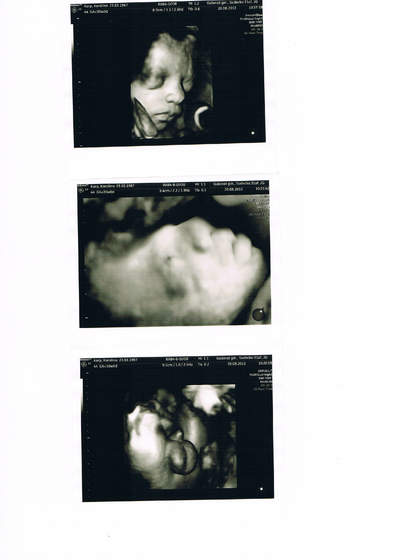

Chwalę się, że byłam dziś na tym darmowym usg- był mój lekarz, ordynator szpitala i dwóch panów od ustawiania sprzętu. Leżałam z głowicą na brzuchu z 35 minut, na dzień dobry ordynator poczęstował nas czekoladą nawet

Świetnie że się załapałam, bo nie wydałabym 200 zł na takie badanie, a tak to młody miał jeszcze dokładniej wszystko zmierzone i sprawdzone, bo ustawiali różne parametry usg, byłam krolikiem doświadczalnym

Pamiątka będzie cudowna, nie wiedziałam że aż tak dokładnie będzie widać Tomka- kurcze zapowiada sie, że będzie bardziej do M. podobny.